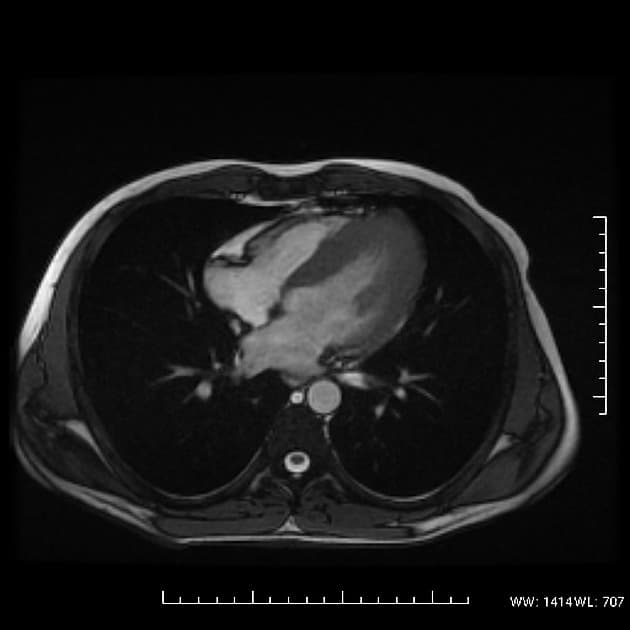

- Bệnh cơ tim phì đại dạng đỉnh thất (apical hypertrophic cardiomyopathy) với tắc nghẽn ở đoạn giữa thất (midventricular obstruction).

- Dạng bệnh cơ tim phì đại do bất thường ở sợi co cơ (sarcomeric hypertrophic cardiomyopathy) này ít gặp hơn so với dạng phì đại không đối xứng điển hình ở vùng trước vách-đỉnh (anteroseptoapical) và cũng ít gặp hơn dạng phì đại ở vùng sau vách (inferoseptal pattern).

- "Bệnh cơ tim phì đại dạng đỉnh thất là thể hiếm, đặc trưng bởi phì đại cô lập ở đỉnh thất trái."

Bệnh cơ tim phì đại dạng đỉnh thất là một thể hình thái riêng biệt của bệnh cơ tim phì đại do bất thường sợi co cơ, chủ yếu ảnh hưởng đến đỉnh thất trái. Khác với thể phì đại vách không đối xứng phổ biến hơn, thể này biểu hiện bằng sự dày lên cô lập ở vùng đỉnh, thường dẫn đến tắc nghẽn đoạn giữa thất và tạo gradient áp lực. Tình trạng căng thẳng huyết động này có thể gây thiếu máu cơ tim vùng đỉnh, hoại tử lớp dưới nội tâm mạc và xơ hóa thành thất dạng ổ, như thấy trên hình ảnh cộng hưởng từ tăng sáng muộn. Sự hiện diện của mô xơ liên quan đến nguy cơ cao hơn về rối loạn nhịp và các biến cố tim bất lợi, làm tiên lượng có thể xấu hơn. Chẩn đoán phân biệt bao gồm nhồi máu cơ tim, bệnh cơ tim do amyloid và sarcoid, nhưng hình ảnh đặc trưng dạng 'bích' trên chụp buồng thất trái và sự vắng mặt của bệnh động mạch vành giúp khẳng định chẩn đoán.